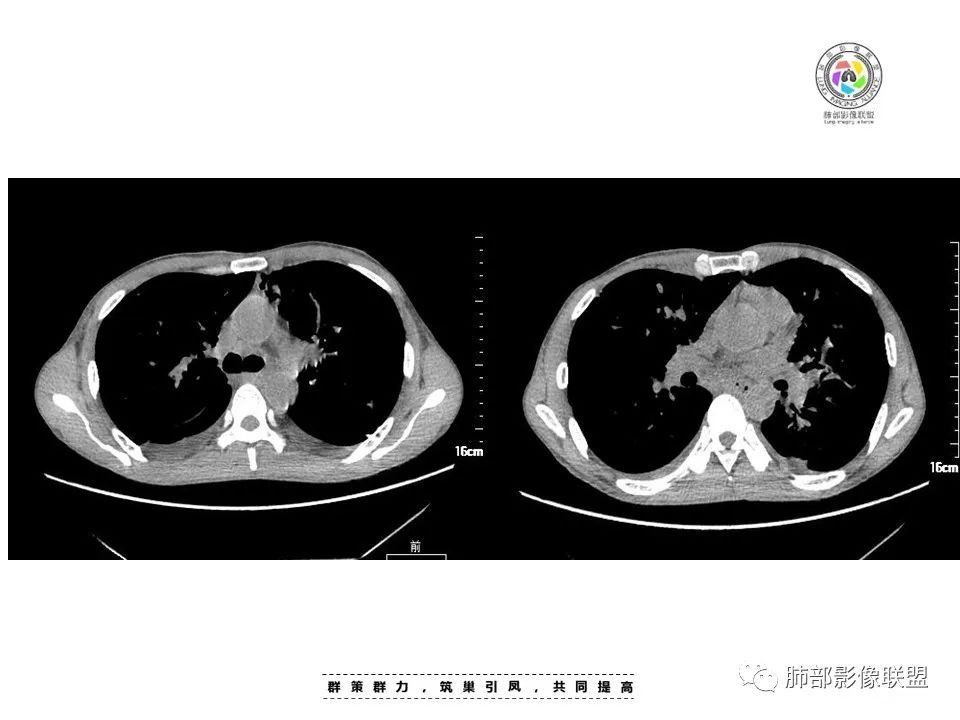

中年男性,发热、全身散在暗紫色丘疹,查CD4+T细胞64个/ul,临床信息提示AIDS并发卡波西肉瘤;CT提示双肺多发实性结节影及毛玻璃结节,部分呈点晕征,右上肺大姐姐边缘膨隆、分叶伴晕;双下肺结节沿支气管血管束分布,中轴间质增粗,部分支气管堵塞,叶间裂结节状增厚,部分结节胸膜下分布,可疑局部小叶间隔增厚,肺部病变呈淋巴分布特点,结合临床肺部病变考虑肺卡波西肉瘤,鉴别淋巴瘤。

2.本例双肺小叶间隔增厚明显,多发结节影及片状实性密度影,沿血管支气管束分布为主,两侧较为对称,病灶多环以磨玻璃晕,边界不清。

双侧胸腔少量积液。双肺门及纵隔未见明确肿大淋巴结,纵隔结构间隙模糊。

3.有学者将这种具有沿双肺支气管束分布的实性密度片影描述为“火焰征”,认为具有一定特征性,单就影像表现而言,这种影像表现也可以见于其他病损或多种病理改变的叠加。

如马尔尼菲篮状菌感染,HIV患者总会联想到它!同样可以出现双肺多发结节影、片影及磨玻璃影,结节影边界也可以较为清楚(甚至可以有点类似结核那种肉芽肿结节),磨玻璃影常见于灶周出血等等。尽管临床实践中马尔尼菲篮状菌感染似乎更多表现为淋巴增大及网质内皮系统损害(如肝脾改变)以及较特有的带有脐凹的皮疹等等。

AIDS型KS皮肤结节分布无规律,临床表现多样,进展迅速,更多见于口腔黏膜,内脏器官,如淋巴结、肺、胃肠道等器官。

1.结节型:两肺沿支气管血管束分布的结节影,呈火焰状或星芒状、挂果征,局部周围出血磨玻璃影(肺泡出血或水肿)。

2.支气管血管束增粗型:

肺门周围支气管壁呈“套袖样”改变。

3.肺炎渗出型:

斑片渗出影,部分融合呈“火焰样”,同时有火焰样结节,小叶间隔增厚等表现。

还可以有纵隔及腋下淋巴结增大,胸腔积液等表现。